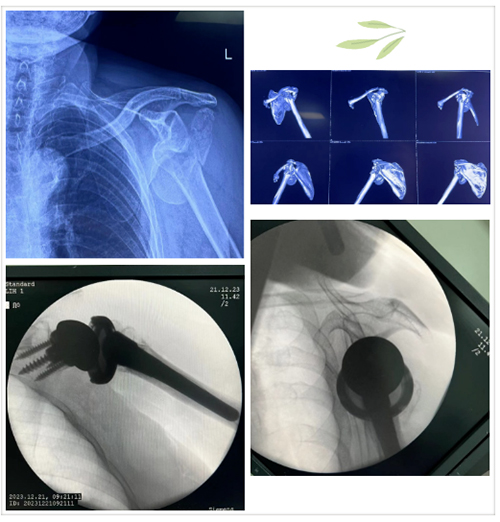

近日,因大面积降雪,导致路面湿滑,摔伤患者数量明显增加,山东第一医科大学附属省立医院(山东省立医院)创伤中心全体医护人员根据医院统筹安排,全力做好摔伤患者救治工作,加班加点进行手术,保障患者生命安全。

12月19日7点多,很多人还在睡梦中,省立医院创伤中心的医生们便已经进入手术室为当天的手术做准备。前一天,科室团队已紧锣密鼓的展开准备工作,确定手术次序、制定手术方案、准备手术器械等。仅这一天,东院创伤中心就安排了20余台手术。

以上手术是创伤中心一天一个病区20余台手术的缩影,科室当天手术一直持续到深夜才结束。山东省创伤中心在山东省内创伤救治工作中始终发挥着引领和带头作用,此次应对大雪后骨折患者激增的情况,山东省创伤中心团队也充分展现了省立医院强大的综合实力、迅捷的救治能力,为山东人民健康保驾护航。